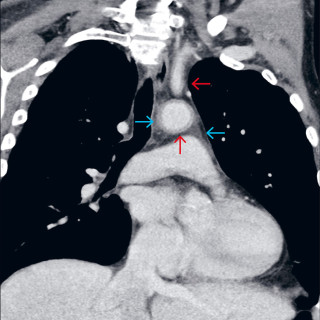

Denne kasuistikken beskriver alvorlig iatrogen botulisme etter behandling med injeksjon av botulinumtoksin ved en privatklinikk i utlandet. En kvinne i 40-årene ble akuttinnlagt i medisinsk avdeling grunnet økende svelgparese, svakhet i nakkemuskulatur, obstipasjon, munntørrhet, hodepine, fatigue, tunge øyelokk og uklart syn de siste fem dager. De siste tre dagene før innleggelsen hadde hun ikke fått i seg flytende eller fast føde, og hodet måtte støttes når hun skulle sette seg opp. Det fremkom at hun 15 dager tidligere hadde fått injisert botulinumtoksin type A mot migreneplager under et...